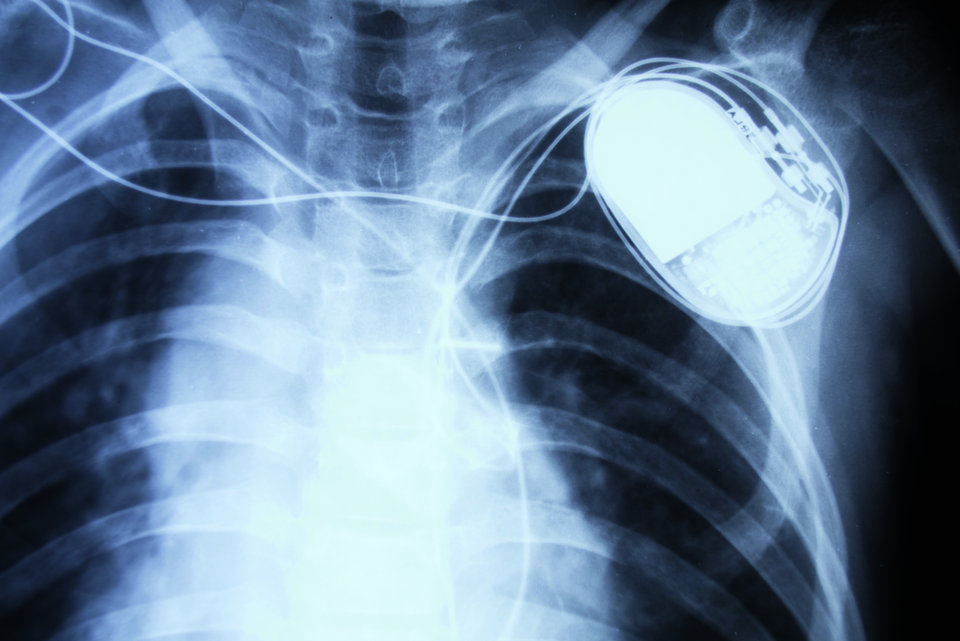

Sind die Minisysteme schon bereit zum Einsatz bei Jedermann? Geringere Invasivität, einfachere Implantation, weniger Komplikationen: Von kabellosen Schrittmachern versprechen Kardiologen sich einiges. Doch sind die Systeme schon tauglich für den klinischen Alltag?

Fortschritte in Elektronik und Energieversorgung (high-density-Batterien) haben es möglich gemacht, miniaturisierte Schrittmachersysteme zu entwickeln. Diese funktionieren ohne Elektrodenkabel und werden transvenös direkt im rechten Ventrikel verankert – wie das MicraTM-TPS (transcatheter pacing system) und das NanostimTM-System. Wie Prof. Philippe Ritter, Hôpital Haut Lévèque, Bordeaux, ausführte, der maßgeblich an der klinischen Evaluation des MicraTM-TPS beteiligt war, sind diese Minisysteme etwa zehnfach kleiner und leichter als konventionelle Einkammer-Schrittmacher.